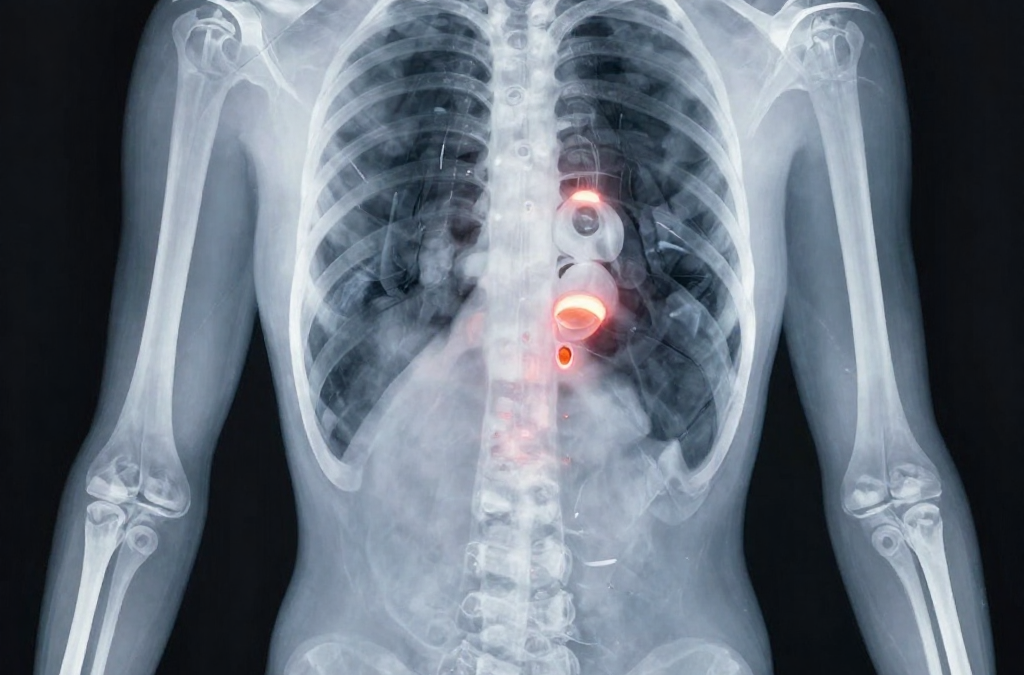

A escoliose idiopática do adolescente (EIA) e a escoliose degenerativa do adulto são condições complexas que afetam milhões de pessoas e suas famílias em todo o mundo. Durante décadas, o tratamento convencional foi baseado na política do “observar e esperar” — o que muitas vezes permitia que a curva progredisse livremente — ou em intervenções extremamente invasivas, como cirurgias de artrodese e o uso de coletes rígidos que causavam grande impacto psicológico e limitações físicas. No entanto, ao chegarmos em 2026, a ciência fisioterapêutica estabeleceu protocolos muito mais sofisticados e eficazes. Na Fisioclínica Caxias, temos o compromisso de ser a referência em Caxias do Sul para o tratamento de escoliose através do método SEAS (Scientific Exercise Approach to Scoliosis). O que torna a Escoliose tão complexa? (A Visão Tridimensional) Para compreender a eficácia de um tratamento, precisamos primeiro entender a natureza da patologia. A escoliose é frequentemente mal compreendida como sendo apenas uma “coluna torta para o lado”. Na realidade, trata-se de uma deformidade estrutural tridimensional. Ela envolve três componentes distintos que ocorrem simultaneamente: Inclinação Lateral: O desvio da coluna para a esquerda ou direita no plano frontal. Rotação Vertebral: As vértebras giram sobre seu próprio eixo, criando a famosa “giba” ou corcunda nas costelas. Alteração Sagital: A perda ou inversão das curvas naturais de perfil, como a retificação da cifose torácica ou da lordose lombar. Por ser uma deformidade que ocorre nos três planos do espaço, qualquer exercício genérico de academia ou alongamento simétrico que tente apenas “empurrar” a coluna lateralmente será ineficaz e, em alguns casos, pode até acelerar a progressão da curva ao aumentar a instabilidade. O SEAS foi desenhado especificamente para responder a cada um desses componentes de forma integrada. A Origem, o Rigor e a Ciência por trás do SEAS O SEAS não é apenas uma “técnica de exercícios”, mas uma abordagem terapêutica desenvolvida na Itália pelo prestigiado Instituto Científico Italiano da Coluna (ISICO). O método é um dos pilares das diretrizes internacionais da SOSORT (Society on Scoliosis Orthopaedic and Rehabilitation Treatment). Ele se destaca globalmente por ser um dos poucos métodos conservadores que possui o Nível I (Excelente) de evidência científica. Isso significa que existem décadas de estudos clínicos randomizados comprovando que a aplicação correta do SEAS é capaz de reduzir significativamente a necessidade de indicação cirúrgica e evitar que curvas pequenas progridam para graus severos. Na Fisioclínica Caxias, a Dra. Adriana Zangali Cioato aplica estes rigorosos protocolos internacionais, oferecendo aos pacientes de Caxias do Sul o mesmo padrão de tratamento encontrado nos centros de excelência da Europa. O Grande Diferencial Estratégico: Autocorreção Ativa Diferente de abordagens tradicionais onde o paciente recebe manobras passivas do fisioterapeuta, o SEAS baseia-se no conceito revolucionário de Autocorreção Ativa. O segredo do sucesso do SEAS em 2026 não reside apenas em “ficar reto” durante a sessão. O verdadeiro objetivo é a neuroplasticidade: treinar o cérebro para aprender a nova posição e reconhecê-la como o novo padrão de normalidade. Através de exercícios de controle neuromotor, o paciente aprende a manter essa autocorreção enquanto realiza tarefas complexas, como caminhar, estudar ou praticar esportes. É uma reeducação do sistema nervoso central aplicada à estrutura óssea. Como funciona a jornada de tratamento na prática? O tratamento na Fisioclínica Caxias é dividido em etapas claras e monitoradas: Avaliação Postural Computadorizada: Utilizamos a fotogrametria e testes clínicos rigorosos para mapear a geometria exata da curva. Desenvolvimento do Plano Individualizado: No SEAS, não existem “protocolos de prateleira”. Cada plano de exercícios é único para o tipo e o grau da curva de cada paciente. Fase de Estabilização: O objetivo é que os músculos estabilizadores profundos aprendam a “segurar” a correção mesmo sob estresse. Integração Funcional: O paciente deve ser capaz de manter sua coluna protegida em todas as atividades do dia a dia. Escoliose no Adulto e na Terceira Idade: Alívio e Funcionalidade Existe um mito de que, após o fim do crescimento ósseo, não há mais nada a ser feito. No adulto, a escoliose pode progredir devido ao desgaste natural dos discos (escoliose degenerativa). Nestes casos, o SEAS é fundamental para gerenciar a dor crônica, melhorar a capacidade respiratória e manter a funcionalidade global, permitindo um envelhecimento ativo e com autonomia. Conclusão: A Escolha pela Excelência e pela Ciência Receber o diagnóstico de escoliose exige uma decisão estratégica. A intervenção precoce com métodos de alta evidência científica é o fator determinante para um futuro de saúde e movimento pleno. Na Fisioclínica Caxias, unimos a experiência prática acumulada desde 2003 com o que há de mais inovador na ciência mundial. A escoliose tem tratamento, e o movimento inteligente e consciente é a única chave real para o sucesso a longo prazo.